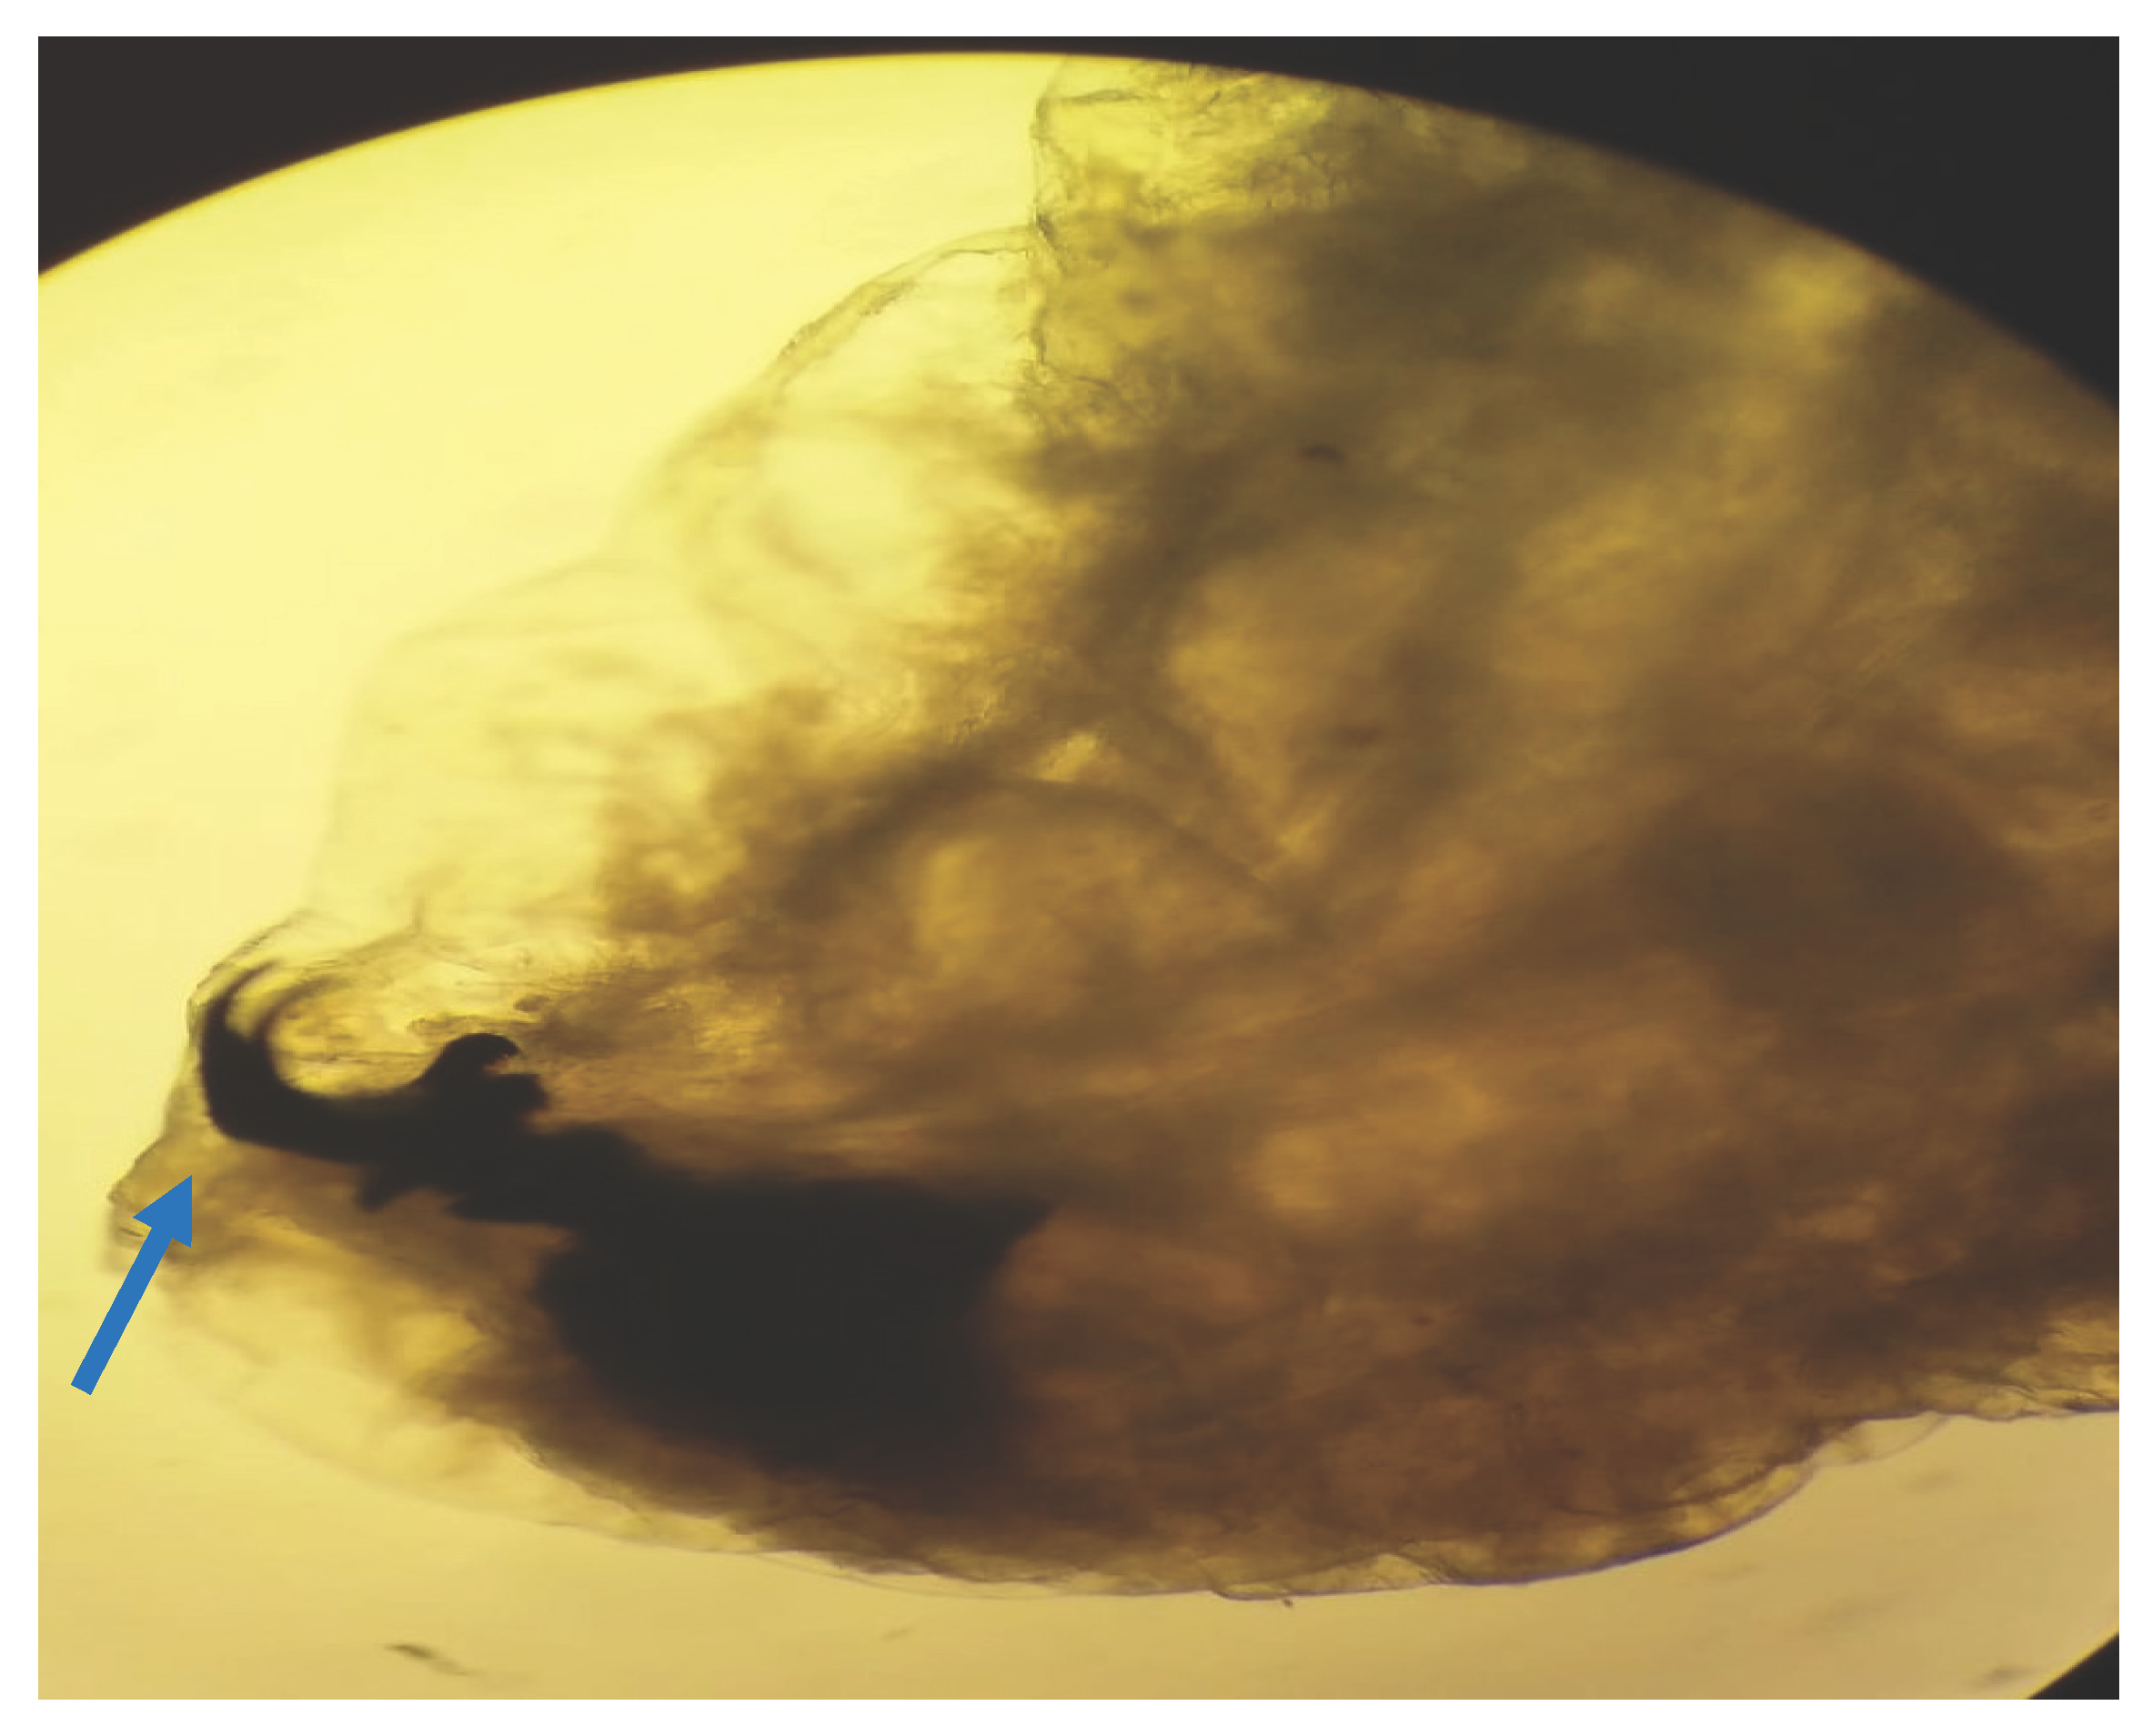

Macroscopic and microscopic examination of the larvae enabled us to identify the species Oestrus ovis according to Zumpt’s criteria. They were L2 stage larvae (between 5 and 6 mm in size) (Figure 1 and Figure 2). The larvae are semi-cylindrical in shape. The posterior respiratory stigmata are subcircular with a central knob and pierced by numerous pores (Figure 3).The pseudocephalon has two buccal hooks (Figure 4).

Figure 4. Anterior extremity of the larva: Mouth hooks (blue arrow) (case 4).